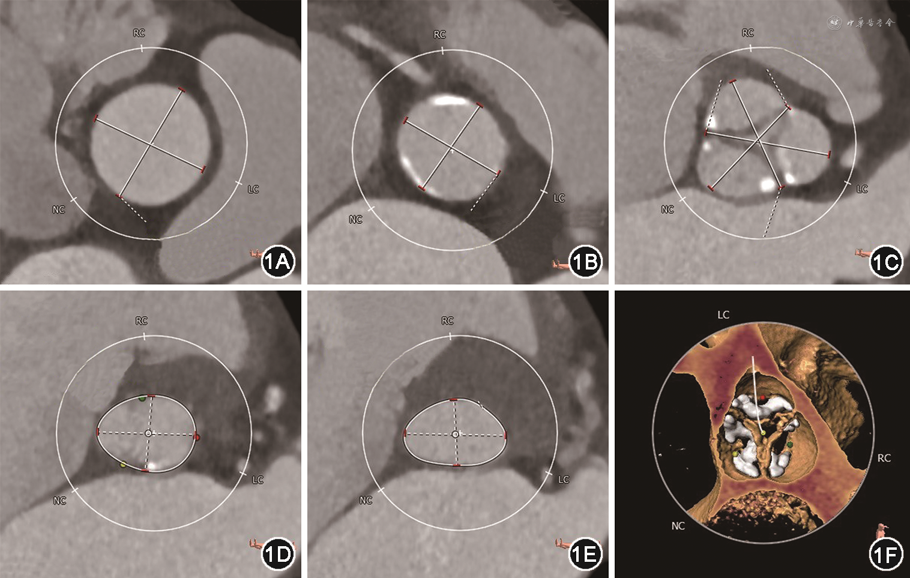

病例1 患者男,83岁,因“反复活动后气促4年余,加重1个月”入院。既往有高血压、心房颤动病史。入院体格检查:主动脉瓣听诊区可闻及收缩期喷射样杂音,二尖瓣区可闻及舒张期隆隆样杂音,双下肺可闻及湿啰音。N末端B型利钠肽原(N-terminal pro-B-type natriuretic peptide,NT-proBNP)10 674 ng/L(参考值0~125 ng/L)。超声心动图提示:风湿性心脏病,重度主动脉瓣狭窄(aortic stenosis,AS)并中-重度关闭不全[主动脉瓣瓣缘结节样增厚,回声增强伴钙化,开放受限,关闭不全,主动脉瓣口血流速度5.0 m/s,峰值压差99 mmHg(1 mmHg=0.133 kPa),反流彩束面积6.0 cm2],重度二尖瓣狭窄(mitral stenosis,MS)并中度关闭不全(二尖瓣瓣尖增厚,回声增强,瓣下结构增粗,前后联合未见明显钙化,开放受限,M型超声心动图示瓣叶呈城墙样改变,瓣口面积0.8 cm2,反流彩束面积7.0 cm2,Wilkins评分为6)。诊断:重度AS,重度MS。患者术前纽约心脏病协会(New York Heart Association,NYHA)心功能分级Ⅳ级,欧洲心脏手术风险评估系统Ⅱ(EuroSCORE Ⅱ)评分为13.26%。术前主动脉CT血管成像(computed tomography angiography,CTA)提示:主动脉瓣为三叶瓣,重度钙化,钙化相对均匀分布在瓣叶上;升主动脉内径31.7 mm,窦管结合部内径26 mm,窦部内径分别为30.5 mm(右冠窦)、32.7 mm(左冠窦)、29.3 mm(无冠窦),主动脉瓣环内径22.2 mm,左心室流出道内径21.7 mm,左、右冠状动脉开口高度分别为15.1、17.8 mm,解剖适合经导管主动脉瓣置换术(transcatheter aortic valve replacement,TAVR)(图1)。